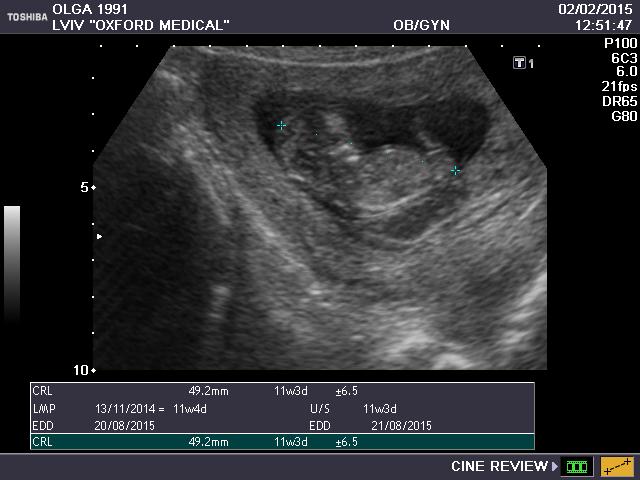

Мои неделькиСегодня были на узи с мужем, он первый раз увидел малявку,жаль не сфоткала его выражения лица)))) Первой фразой было "он там так прыгает,как ты не чувствуешь?")))))Я то уже неделю назад виделась с крохой(непонятно зачем врач не предупредила что на скрининг надо будет делать еще узи, я ы не делал 2 подрят). На этот раз врач предположила нам мальчика( делала узи другой врач). Будет папин сыночек, все личиком поворачивался и махал ручкой папе, ко мне попкой поворачивался прошлый раз))))Но я не в обиде)) По показателям все у нас тьфу-тьфу хорошо) Завтра сдаю кровь))Вот так малыш передает привет